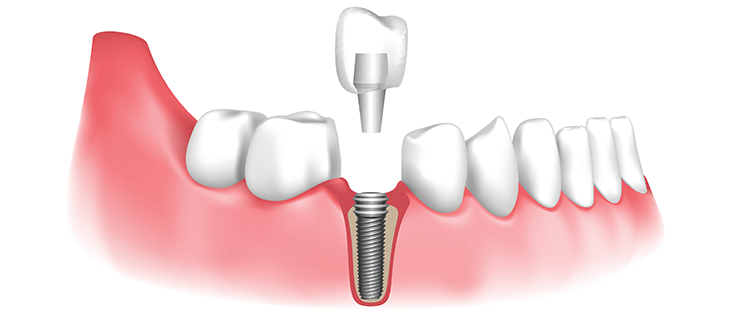

Un implant dentaire est une racine artificielle, généralement en titane, insérée dans l’os de la mâchoire pour remplacer la racine d’une dent naturelle manquante. Il sert de base solide pour fixer une couronne, un bridge ou une prothèse.

Les composants d’un implant

- 🔹 L’implant : vis en titane insérée dans l’os

- 🔹 Le pilier : connecte l’implant à la couronne

- 🔹 La couronne : partie visible qui imite la dent naturelle

Étapes de la pose d’un implant dentaire

- Consultation initiale : évaluation de la santé bucco-dentaire et radiographie

- Plan de traitement personnalisé : choix du type d’implant adapté

- Pose de l’implant : chirurgie sous anesthésie locale

- Période de cicatrisation : 3 à 6 mois pour l’ostéo-intégration

- Pose de la couronne : restauration esthétique et fonctionnelle